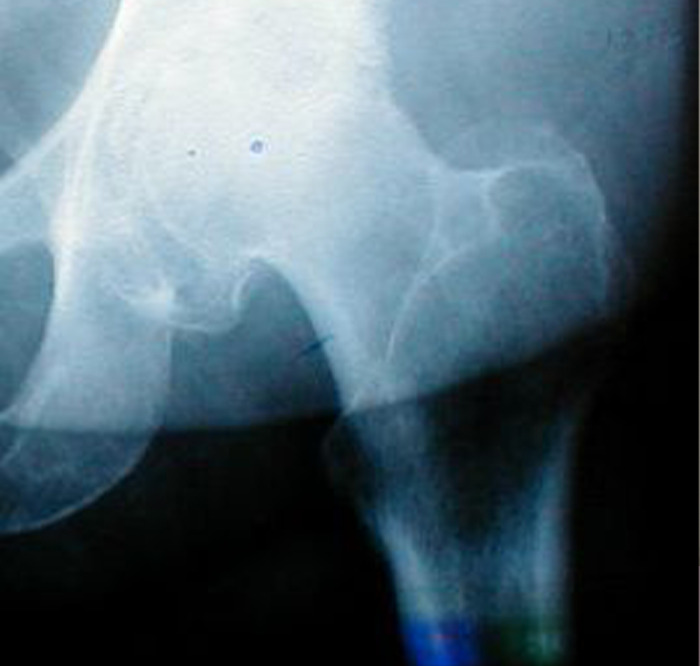

My grandmother had her hip replaced, but the hip always hurt to her. She waited a year, hoping it would go away but it never did, she asked multiple doctors and did multiple x-rays but doctors said the replaced hip was fine. We finally made her go to a private clinic in my hometown, and the doctor saw that the replaced hip was fine and dandy, but the bone around it looked like it was a tad bit eaten by bacteria.

So the new doc did an operation, and there was so much pus in the leg it was insane. If my grandmother waited any longer, her blood would become infected and she would have died.